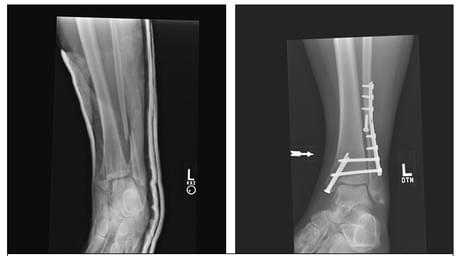

Переломы лодыжек следует дифференцировать с повреждением связок голеностопного сустава. При переломах боль, как правило, локализуется выше, максимальная болезненность определяется при пальпации костей, а не мягкотканных образований. Для постановки окончательного диагноза назначается рентгенография голеностопного сустава в двух стандартных проекциях (боковой и переднезадней). На снимках определяются линии изломов, направление и степень смещения отломков, вид подвывиха и степень расхождения берцовых костей. В сомнительных случаях назначают КТ голеностопного сустава, при необходимости оценить состояние мягкотканных структур - МРТ голеностопного сустава.

Внутреннюю лодыжку фиксируют двухлопастным гвоздем или винтами. При разрывах межберцового синдесмоза производят сближение берцовых костей, используя длинный винт или специальный болт. Для фиксации наружной лодыжки применяют гвоздь или спицу. При переломах заднего и переднего края производят остеосинтез лодыжек винтом или гвоздем. Затем рану послойно ушивают и дренируют, на ногу накладывают гипс. В послеоперационном периоде проводят антибиотикотерапию, назначают анальгетики, УВЧ и лечебную физкультуру. После снятия гипса осуществляют мероприятия по разработке сустава.